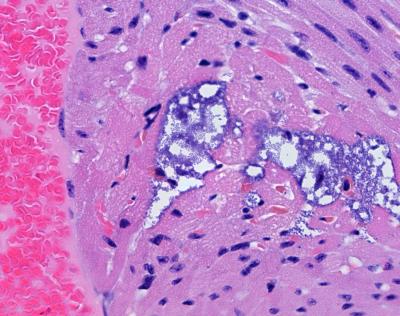

The researchers found proof that Streptococcus pneumoniae, the leading cause of community-acquired pneumonia, actually physically damages the heart. The bacterium leaves tiny lesions that researchers detected in mouse, rhesus macaque and human autopsy tissue samples.

Streptococcus pneumoniae in the blood invaded the heart and formed lesions in the myocardium, the muscular middle layer of the heart wall, the researchers showed. The team identified mechanisms by which the bacterium is able to spread across endothelial cells in cardiac blood vessels to travel to and infect the heart.